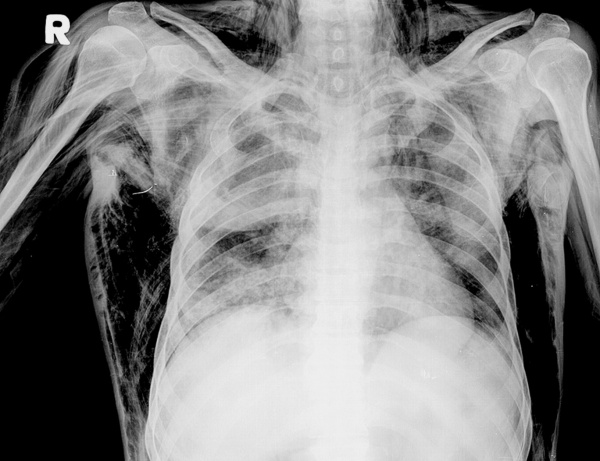

- Рентгенография. При патологиях ОГК обязательно делают обзорный снимок, опционально – прицельный. Возможно обнаружение переломов ребер, гемо- и пневмоторакса, пневмомедиастинума. При травмах лица выполняют рентгенограммы орбиты, костей носа, скуловой кости. Иногда требуется рентгенография черепа для исключения переломов его мозговой части.

Диагностика буллезной эмфиземы легких основывается на клинических, функциональных и рентгенологических данных. Курация больного осуществляется пульмонологом, а при развитии осложнений – торакальным хирургом. Рентгенография легких не всегда эффективна в выявлении буллезной эмфиземы легких. В то же время, возможности лучевой диагностики существенно расширяет внедрение в практику КТ высокого разрешения. На томограммах буллы определяются как тонкостенные полости с четкими и ровными контурами. При сомнительном диагнозе удостовериться в наличии булл позволяет диагностическая торакоскопия.